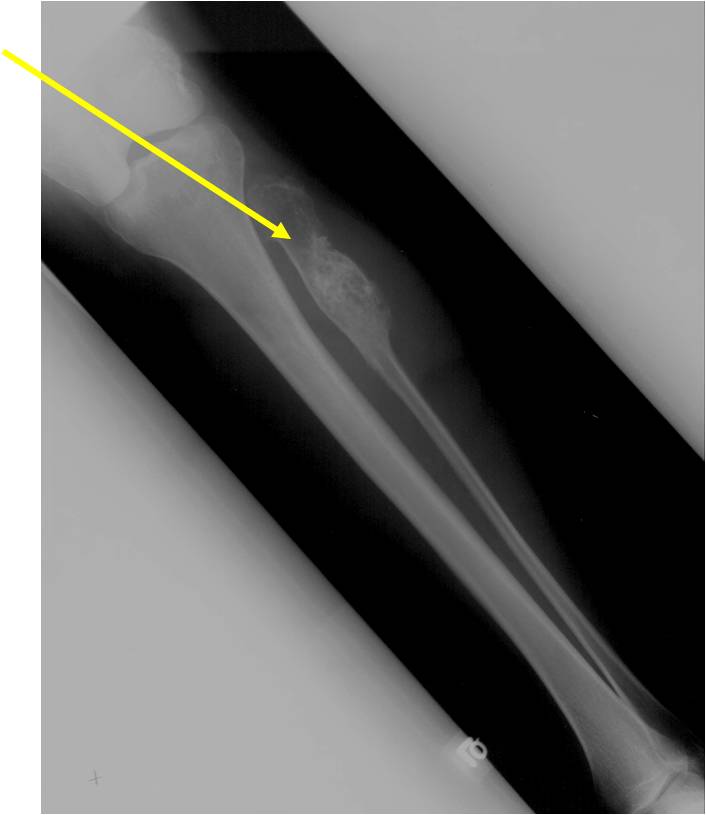

- Localized, radiolucent defect usually with punctate calcifications

- Calcifications are stippled, punctate, popcorn like calcifications and “Ring and Arc” calcifications

- Most commonly found in metaphysis

- Geographic lytic lesion

- Expansile remodeling with thinned cortex

- Chondroid matrix with calcifications in majority of tumors

Enchondromatosis

- Enchondromatosis is a rare disorder that is not hereditary in which the patient is afflicted with multiple intraosseous cartilaginous tumors or enchondromas.

- May be predominantly unilateral or affect a single extremity/limb

- Affected limb is often shortened and deformed and angulated

Enchondromas in enchondromatosis may involve the metaphysis, diaphysis, epiphysis and articular cartilage

- Hypercellular with large number of binucleated chondrocytes

- Higher degree of cellularity and atypia compared to isolated enchondroma